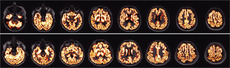

Fitting regression models can be challenging when regression coefficients are high-dimensional. Especially when large spatial or temporal effects need to be taken into account the limits of computational capacities of normal working stations are reached quickly. The analysis of images with several million pixels, where each pixel value can be seen as an observation on a new spatial location, represent such a situation. A Markov chain Monte Carlo (MCMC) framework for the applied statistician is presented that allows to fit models with millions of parameters with only low to moderate computational requirements. The method combines a modified sampling scheme with novel accomplishments in iterative methods for sparse linear systems. This way a solution is given that eliminates potential computational burdens such as calculating the log-determinant of massive precision matrices and sampling from high-dimensional Gaussian distributions. In an extensive simulation study with models of moderate size it is shown that this approach gives results that are in perfect agreement with state-of-the-art methods for fitting structured additive regression models. Furthermore, the method is applied to two real world examples from the field of medical imaging.